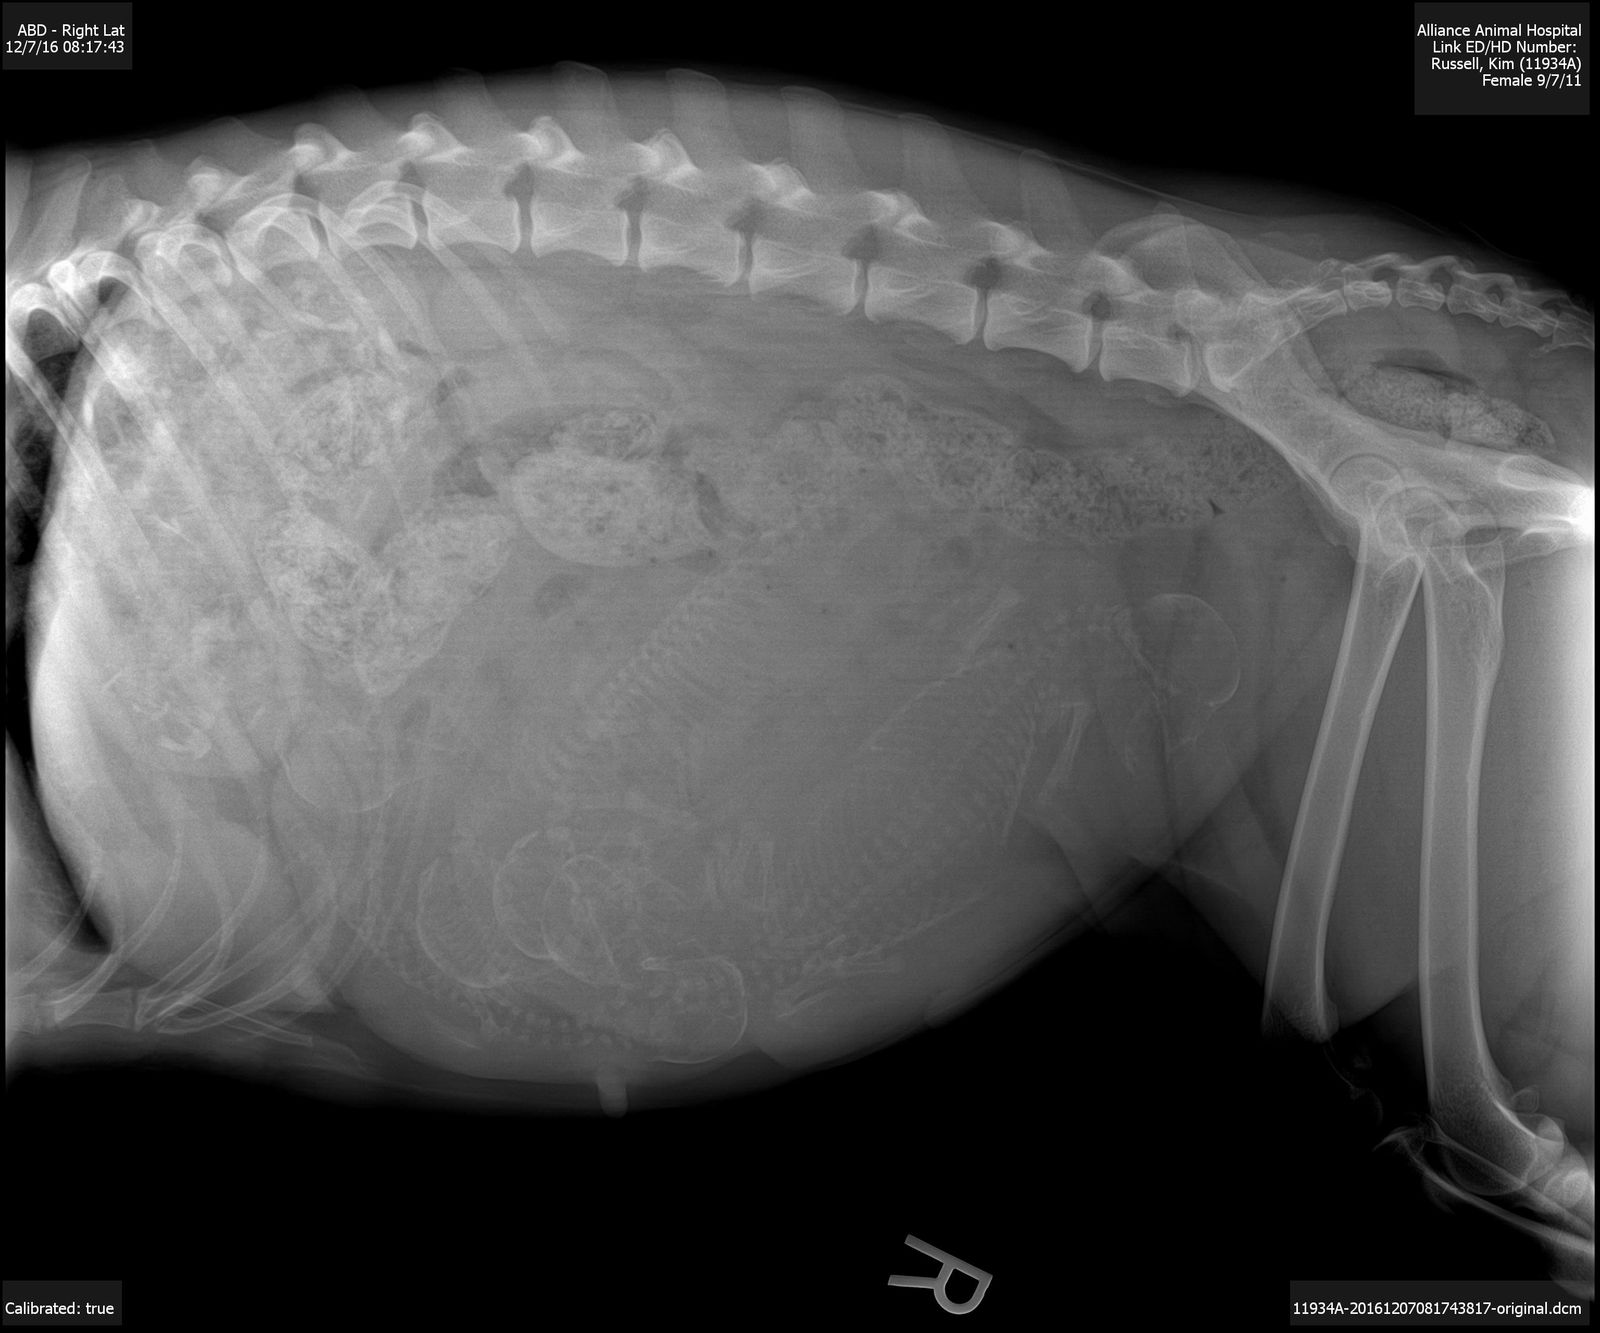

Link and Fly welcomed six BEAUTIFUL babies into the world December 15, 2016.